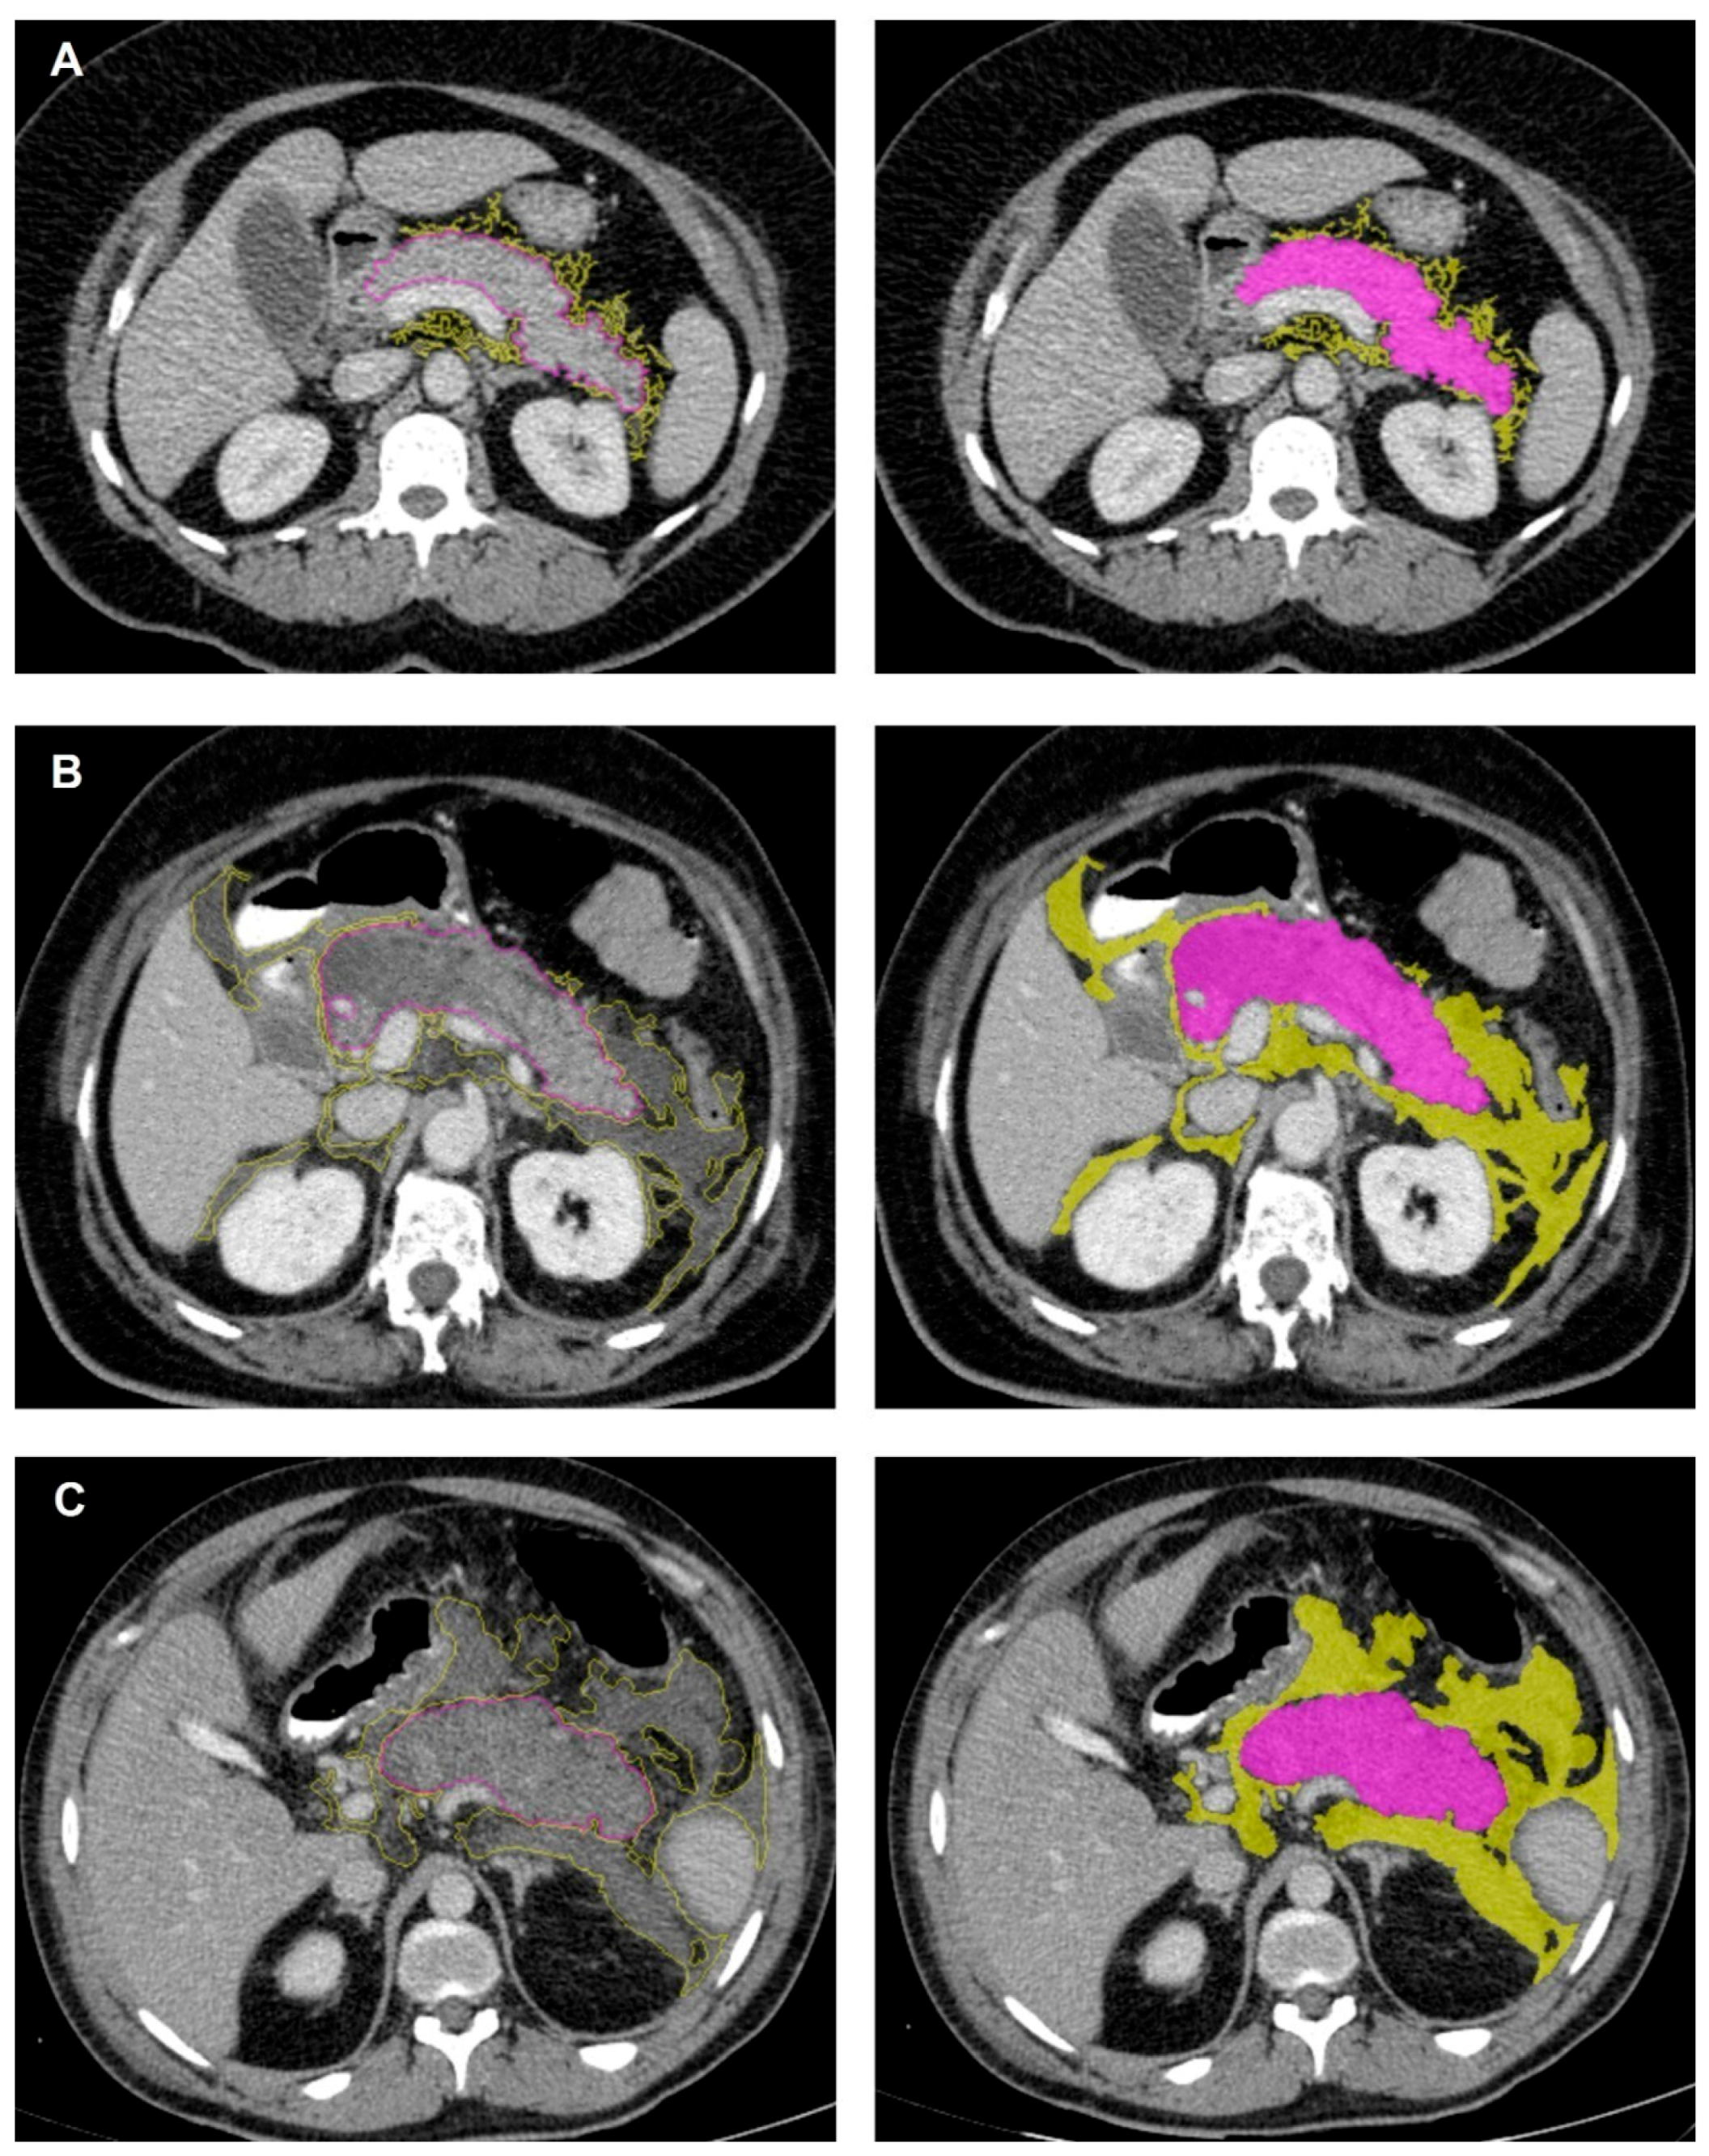

2.3. CT Image Interpretation and Feature Extraction